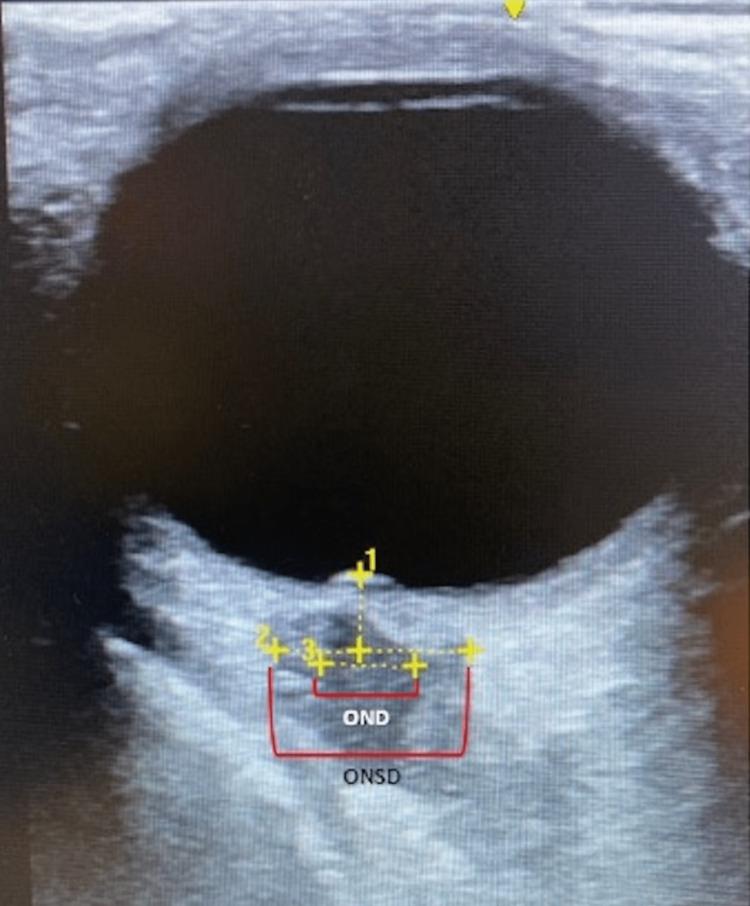

Ultra-low-dose combination estrogen-progestin contraceptive pills (OCP) have been marketed as being safer to use than previously higher estrogen-containing OCPs. While multiple large studies have shown a dose-dependent association between estrogen and deep vein thrombosis, there remains sparse guidance or data as to whether patients with sickle cell trait should avoid estrogen-containing OCPs regardless of the dosage. We present a case of a 22-year-old female with a history of sickle cell trait who had recently been started on an ultra-low-dose norethindrone-ethinyl estradiol-iron (1-20 mcg) that presented with headache, nausea, vomiting, and obtunded. Initial neuroimaging was significant for an extensive superior sagittal sinus thrombosis with extension into the confluence of dural venous sinuses, right transverse sinus, right sigmoid sinus, and right internal jugular vein which ultimately required systemic anti-coagulation. Her symptoms largely resolved within four days after starting anti-coagulation. She was discharged on day six to complete a six-month course of oral anti-coagulation. At her neurology follow-up three months later, the patient reported resolution of all symptoms. This study evaluates the safety of ultra-low-dose estrogen-containing contraceptive pills in the sickle cell trait population with special focus on cerebral sinus thrombosis.

超低剂量复方雌激素 - 孕激素避孕药(口服避孕药)已上市销售,宣传称其使用起来比以前含雌激素量更高的口服避孕药更安全。虽然多项大型研究表明雌激素与深静脉血栓形成之间存在剂量依赖性关联,但对于携带镰状细胞性状的患者是否应避免使用含雌激素的口服避孕药(无论剂量如何),仍然缺乏相关指导或数据。我们报告一例22岁有镰状细胞性状病史的女性病例,她最近开始服用超低剂量的炔诺酮 - 炔雌醇 - 铁(1 - 20微克),出现头痛、恶心、呕吐和意识模糊症状。最初的神经影像学检查显示广泛的上矢状窦血栓形成,并延伸至硬脑膜静脉窦汇合处、右侧横窦、右侧乙状窦和右侧颈内静脉,最终需要进行全身抗凝治疗。在开始抗凝治疗后的四天内,她的症状基本缓解。她在第六天出院,完成为期六个月的口服抗凝疗程。在三个月后的神经科随访中,患者报告所有症状均已消失。本研究评估了超低剂量含雌激素避孕药在镰状细胞性状人群中的安全性,特别关注脑窦血栓形成。